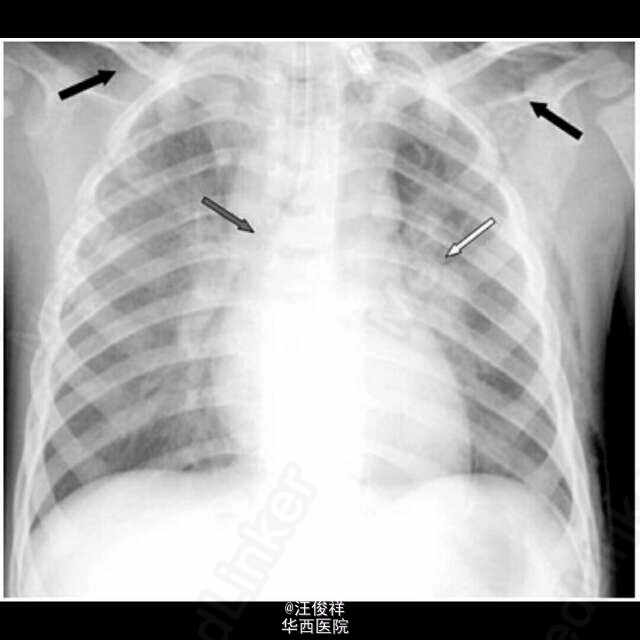

以皮下气肿为症状的结核病很罕见,在儿童中往往见于粟粒性肺结核的病人。 一个26月大的男孩子因为颈部,面部,躯干上半部分肿胀数小时数入院。触诊发现皮下气肿,呼吸系统检查发现左胸壁的爆裂音,但是没有纵膈偏移。胸部平片示:左肺门扩大伴有纵膈积气和广泛的皮下气肿。支气管镜检查排除了异物吸入的可能,但是显示左主支气管被干酪样物质部分阻塞和肉芽肿的明显表现。增强CT示皮下气肿和纵膈积气,双侧肺门淋巴结病变穿透了邻近组织,左主支气管壁严重受损,空气进入皮下和纵膈。结核菌素试验和支气管和胃液PCR实验均证实结核杆菌阳性。给予抗结核治疗后病情好转。